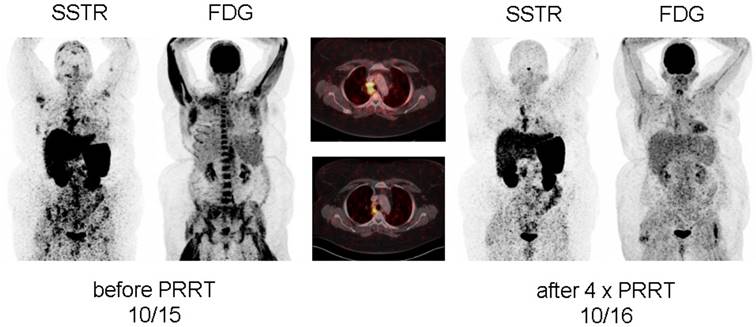

After achieving a pronounced reduction of pain during rest, significantly decreased tracer accumulation in all osseous lesions as well as mediastinal lymph nodes at first restaging 8 weeks after the first treatment cycle, patient #1 demonstrated a very good response after completion of all 4 PRRT cycles with nearly complete resolution of sarcoidosis activity at both [18F]FDG and [68Ga]DOTATOC-PET/CT (Figure 1, Supplementary Figure 1). In parallel, serum levels of neopterin, ACE and soluble interleukin-2 receptor as well as the demand for pain relief had significantly dropped (Table 1, Supplementary Figure 2). Most importantly, the patient reported on sustained well-being after the end of therapy. The effects of PRRT were still present 3 months after end of PRRT without initiation of any other treatment and are still ongoing at the time present (10 months after completion of PRRT).

Figure 1

Display of [18F]-FDG-PET/CT and somatostatin receptor-directed PET/CT with [68Ga]-DOTATOC before and 1 year after initiation of peptide receptor radionuclide therapy with [177Lu] in patient #1. A total of four cycles have been administered. Both PET projections are displayed with the same intensity. Of note, initial bone marrow involvement is more patchy in [68Ga]-DOTATOC-PET/CT as compared to the more diffuse uptake of [18F]-FDG.